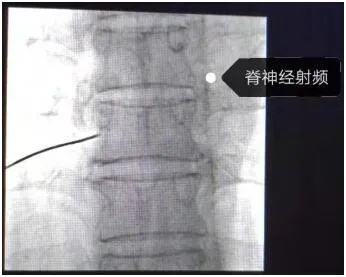

超声+X线双引导下椎间孔脊神经脉冲射频微创介入手术